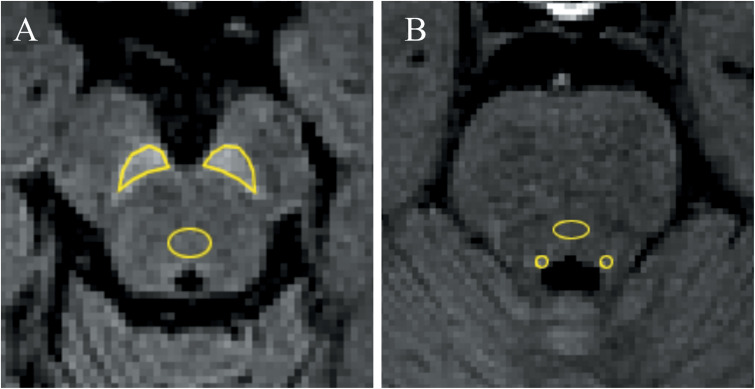

Methods: Neuromelanin images with MT pulse and SPIR (flip angles [FAs] = 19º, 22º, and 25º) were acquired from 30 healthy volunteers. To achieve the same acquisition time of 5 min, the slab thickness of the MT images was less than 1/3 of those of the SPIR images; the acquisition areas for MT and SPIR were the brainstem and the whole brain, respectively. Visual and quantitative evaluation was performed and compared on the four sequences acquired for the substantia nigra pars compacta (SNc) and the locus coeruleus (LC). For visual assessment, we used the mean score from a 3-point scale by two evaluators. For quantitative evaluation, the contrast ratios of SNc and LC were calculated in comparison with the background tissue signal.

Results: In visual assessments, the mean scores of the SPIR FA19º and FA22º images were better than others in the SNc. Regarding LC, the SPIR FA22º image yielded the best mean score. In quantitative evaluations, the MT image was significantly lower than the other three images in SNc. Regarding LC, there were no significant differences among the four acquired images (MT and SPIR FA19º, FA22º, and FA25º).

Conclusions: Detection of neuromelanin in SNc and LC was improved by the use of SPIR compared to MT pulse in 3D neuromelanin imaging.